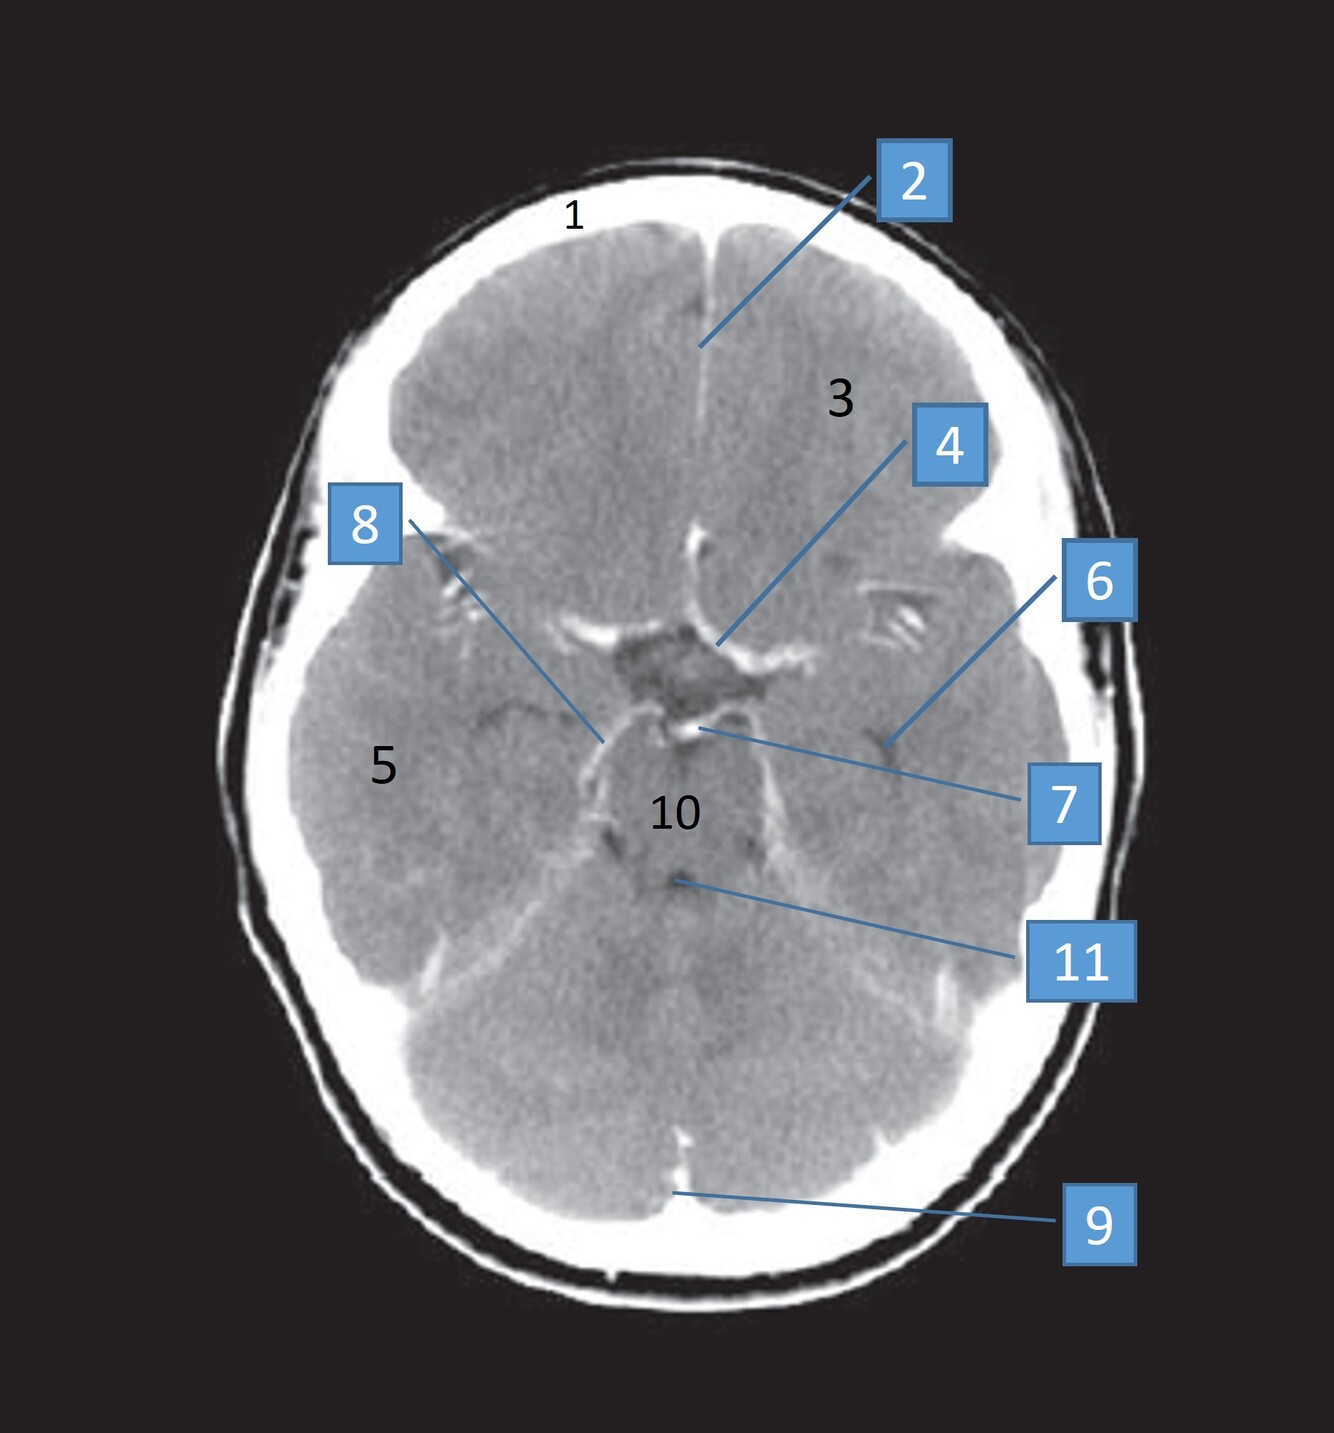

5

Q

Label 2,3,4,5,7,8

A

2=Rt Caudate nucleus

3=Corpus callosum

4=Lt lateral ventricle

5=Third ventricle

7= Septum Pellucidum

8= Rt Interventricular foramen